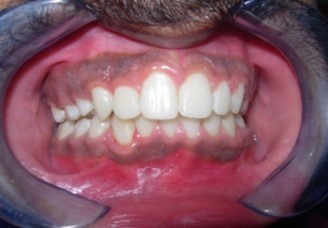

The soft tissue frontal and profile improved dramatically. (Figure 7a-b). The bilateral posterior crossbite was corrected. The severe increase in overjet of about 13mm was effectively reduced to 3mm and the severe deep bite was also corrected (Figure 7c,Figure 7d). Fixed maxillary and mandibular lingual retainers were given. (Figure 7e, Figure 7f). Post orthodontic treatment, normal root inclinations of the teeth and normal alveolar bone levels was observed. (Figure 8).

Figure 7c.Post-treatment intra-oral-Frontal

Post-treatment intra-oral-Frontal

Figure 7d.Post treatment intra-oral – Right

Post treatment intra-oral – Right

Figure 7e.Post-treatment intra-oral-Upper occlusal

Post-treatment intra-oral-Upper occlusal

Figure 7f.Post-treatment intra oral-Lower occlusal

Post-treatment intra oral-Lower occlusal